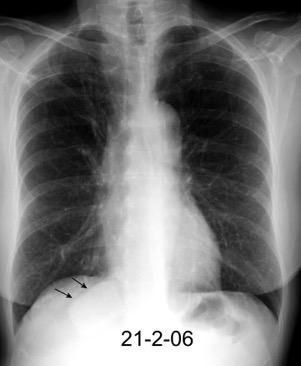

En relación con trasudados tabicados. Insuficiencia cardiaca

Hipoalbuminemia

Cirrosis / Fallo renal.

Operado aneurisma (prótesis). Líquido tabicado en cisuras

Fernandes de Paula MC et al. Focal pleural tumorlike conditions: Nodules and masses beyond mesotheliomas and metastasis. Respiratory Medicine 2015.

Derrame pleural “encapsulado”

“Tumor fantasma”

Asociado a fallo cardiaco. ( “Pleuritis adhesiva”). Buch KP. Chest. 2000